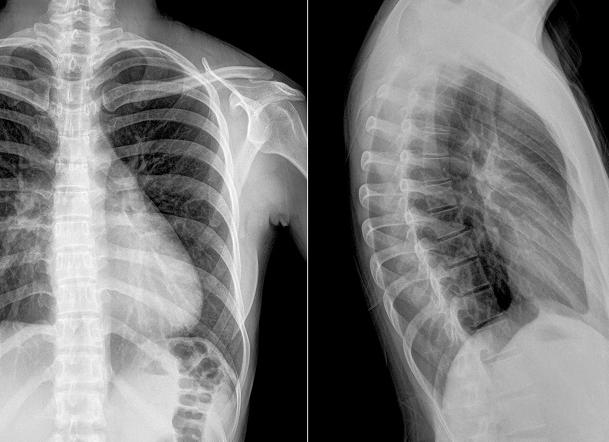

Рентгенограмма грудного отдела позвоночника

Рентгеновское исследование — один из самых распространенных способов выявления патологий опорно-двигательного аппарата. Рентген грудного отдела позвоночника позволяет врачу сделать вывод о нарушениях строения позвоночника в этом отделе.

Для более точной диагностики исследование проводят в двух проекциях:

Что можно увидеть на снимке?

Что показывает рентген:

• состояние суставных щелей;

• наличие или отсутствие переломов, смещений;

• состояние костной ткани позвонков;

• состояние поверхностей позвонков;

• форму позвонков;

• размеры и расположение остистых отростков позвонков.

Рентгеновское исследование не показывает мышцы и связки, а также мягкие ткани, патология которых также может быть источником болезненных ощущений. Поэтому если рентгенограмма показала отсутствие патологий, а боли при движениях есть, то необходимо провести исследования, которые определят состояния мышц и связок.

Т.к. обследование показывает все патологии костной и хрящевой системы, на снимках можно выявить следующие заболевания:

• остеохондроз;

• сколиоз;

• переломы;

• опухоли позвоночника;

• смещения позвонков;

• патологические изменения костной ткани позвоночника;

• туберкулез позвоночника;

• нарушения строения суставов;

• протрузии;

• истончение межпозвоночных дисков;

• генетические аномалии позвоночного столба;

• трещины позвонков;

• аутоиммунные патологии — болезнь Бехтерева, ревматоидный артрит, ревматизм.

Рентгеновский снимок — это черно-белое изображение, где белые участки — это костная ткань. Хрящевая ткань на изображениях не видна, однако толщину межпозвоночного диска врач может определить по расстоянию между позвонками. Различные темные пятна могут указывать на новообразования.

Рентгенография грудного отдела позвоночника

Это исследование дает возможность получить подробное изображение грудных позвонков. По изображениям врач будет судить о состоянии межпозвоночных дисков, наличии искривления позвоночника, а также других деформаций органа.

Рентген дает возможность увидеть:

• все грудные позвонки;

• патологические искривления позвоночника;

• наличие новообразований в позвоночнике;

• поражение грудного отдела инфекционным процессом.

Обычно бывает, что нижние два или три позвонка не видны на снимке отчетливо. Это связано с тем, что они перекрываются плотными тканями органов брюшной полости.

Нужно учесть и то, что при развитии выраженного кифоза грудного отдела изображение позвонков может значительно искажаться.

Исследование грудных позвонков

Что показывает рентген грудного отдела позвоночника? Зачастую приходится прибегать к диагностике посредством рентгена, чтобы обнаружить:

• деформацию отдельных позвонков;

• наличие изменений в костных структурах, характерных для остеохондроза;

• патологию межпозвонковых дисков реберно-позвонкового сочленения;

• опухолевый процесс;

• последствия травматического повреждения позвоночника;

• аномальное развитие позвонков;

• наличие остеопороза (снижение плотности костной ткани).